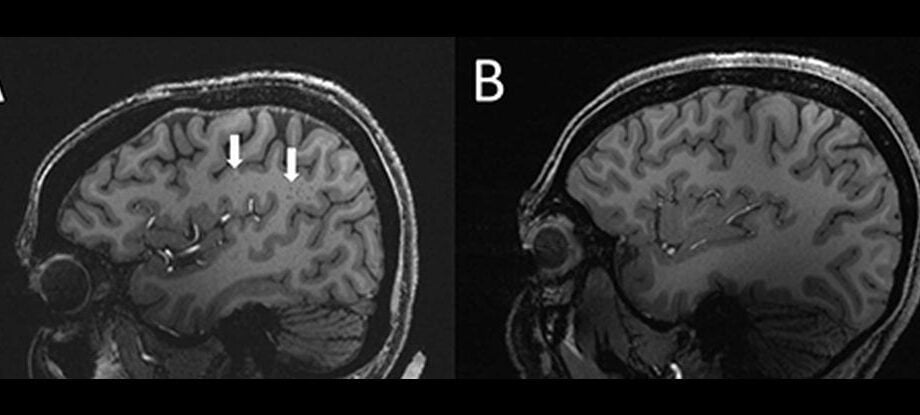

Os cientistas podem ter acabado de encontrar uma nova pista importante que pode ajudar a resolver o mistério frustrante e contínuo da enxaqueca. Com informações de Science Alert. Usando ressonância magnética de ultra-alta resolução , os pesquisadores descobriram que os espaços perivasculares – espaços cheios de líquido ao redor dos vasos sanguíneosContinue Reading